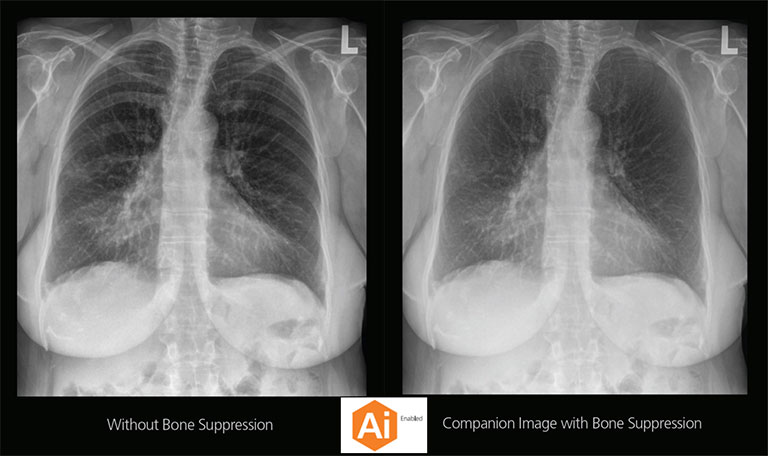

Carestream Introduces New Software Update to Boost Diagnostic Accuracy

Carestream today announced the latest update to its Image Suite V4 Software, MR 11: a series of enhancements to help improve customer confidence and increase diagnostic accuracy [...]